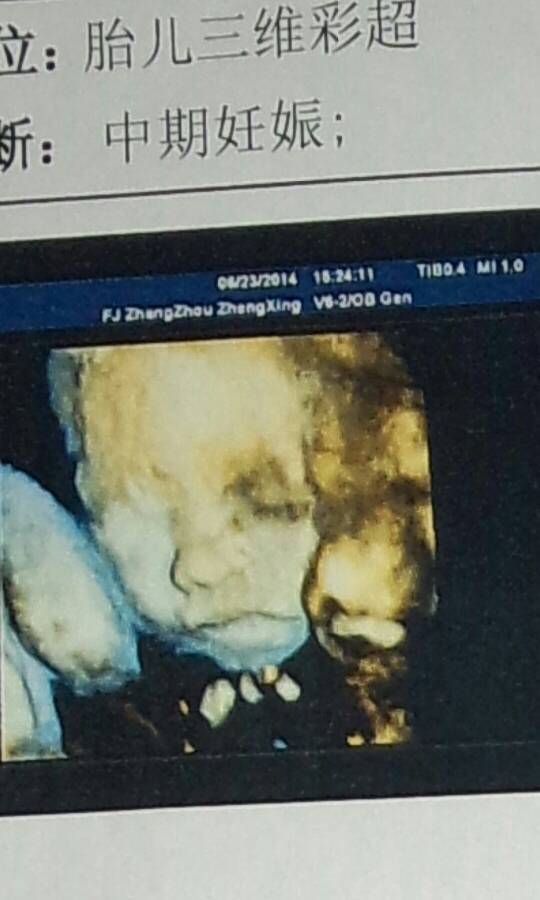

上次去检查的四维彩超,医生说是单活胎,可看图片怎么感觉像是两个脸靠一起的? 点击展开 匿名用户 2020-08-26 06:01 为您推荐: 其他回答 你好,宝宝长的很漂亮的呢,自己这个时候是不用担心的呢,多注意休息一下的啊,这样是会更好的呢 可靠的悠闲80 2020-11-01 21:14 相关问题 医生看四维彩超的图片能看出男女嘛 医生给我们看看,有图片,我们宝宝脸是怎么了,在有两天满月 宝宝脸上长这红色小痘(图片),怎么回事?需要看医生吗?